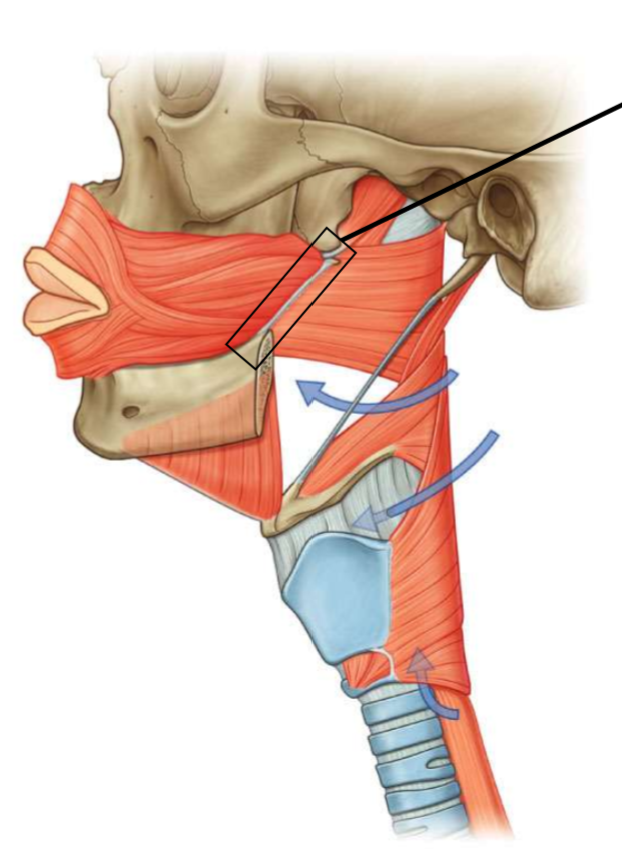

What is the function of the longitudinal/“-pharyngeus” muscles?

elevates the pharyngeal wall

What is this muscle?

stylopharyngeus

What are the attachments of this muscle?

medial surface of the styloid process → deep pharyngeal wall

What innervates this muscle?

glossopharyngeal nerve

What muscle is this?

salpingopharyngeus

What are the attachments of this muscle?

cartilage of the pharyngotympanic tube → deep pharyngeal wall

What innervates this muscle?

vagus nerve

What muscle is this?

palatopharyngeus

What are the attachments of this muscle?

upper surface of palatine aponeurosis → deep pharyngeal wall

What is the function of this muscle?

closes the oropharyngeal isthmus by depressing the palate